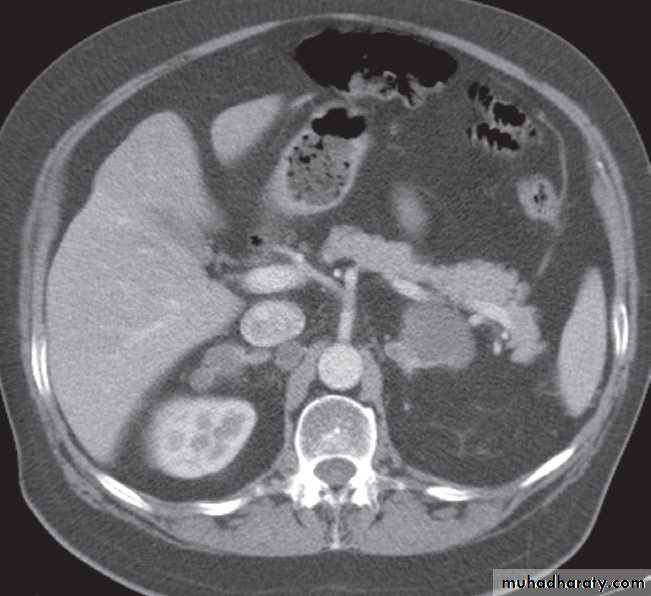

-Renal cell carcinomas are approximately spherical and often lobulated .With density similar to renal parenchyma or slightly less with often seen some areas of necrosis & calcification .

Staging of renal cell carcinoma is usually undertaken with CT, the current method of choice .